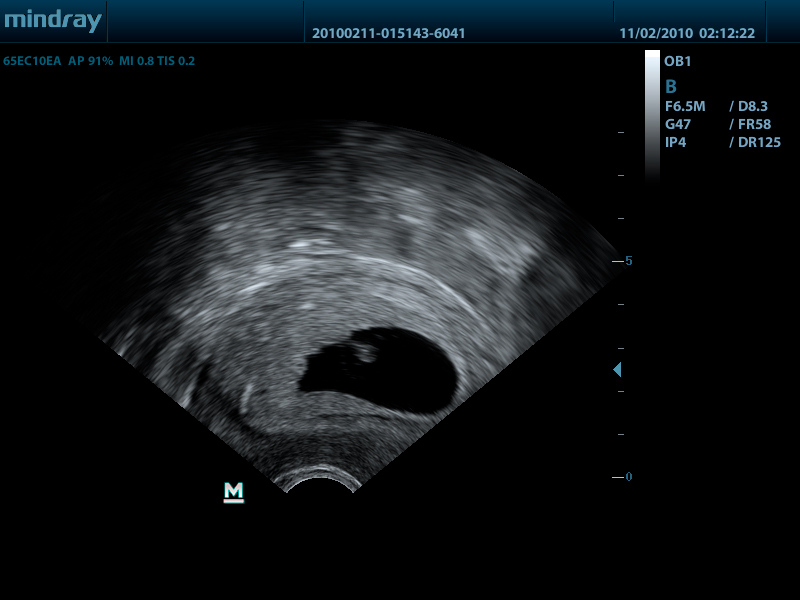

Mindray DP-50 – портативная цифровая ультразвуковая система с ЖК монитором 15 дюймов (1024Х768)

и встроенными аккумуляторными батареями (опция) позволяющими работать в автономном режиме до 2-х часов.

DP-50 – портативный УЗИ сканер разработан на базе новой платформы X-treme engine, используемой в хорошо зарекомендовавших себя цветных сканерах с доплером моделей DC-3, DC-7, DC-6. Эта платформа открывает возможности для расширений до уровня цветных сканеров и совместимости с широким диапазоном периферийного оборудования. X-treme означает интеллект, высокую скорость обработки данных, многоуровневую передачу сигналов, а также возможность оптимизации изображения и модульного расширения.

Применяемые датчики DP-50:

Внутриполостной датчик 65EC10EA (5.0/6.5/7.5/8.5/Н8.0/Н9.0 МГц, R-10 )